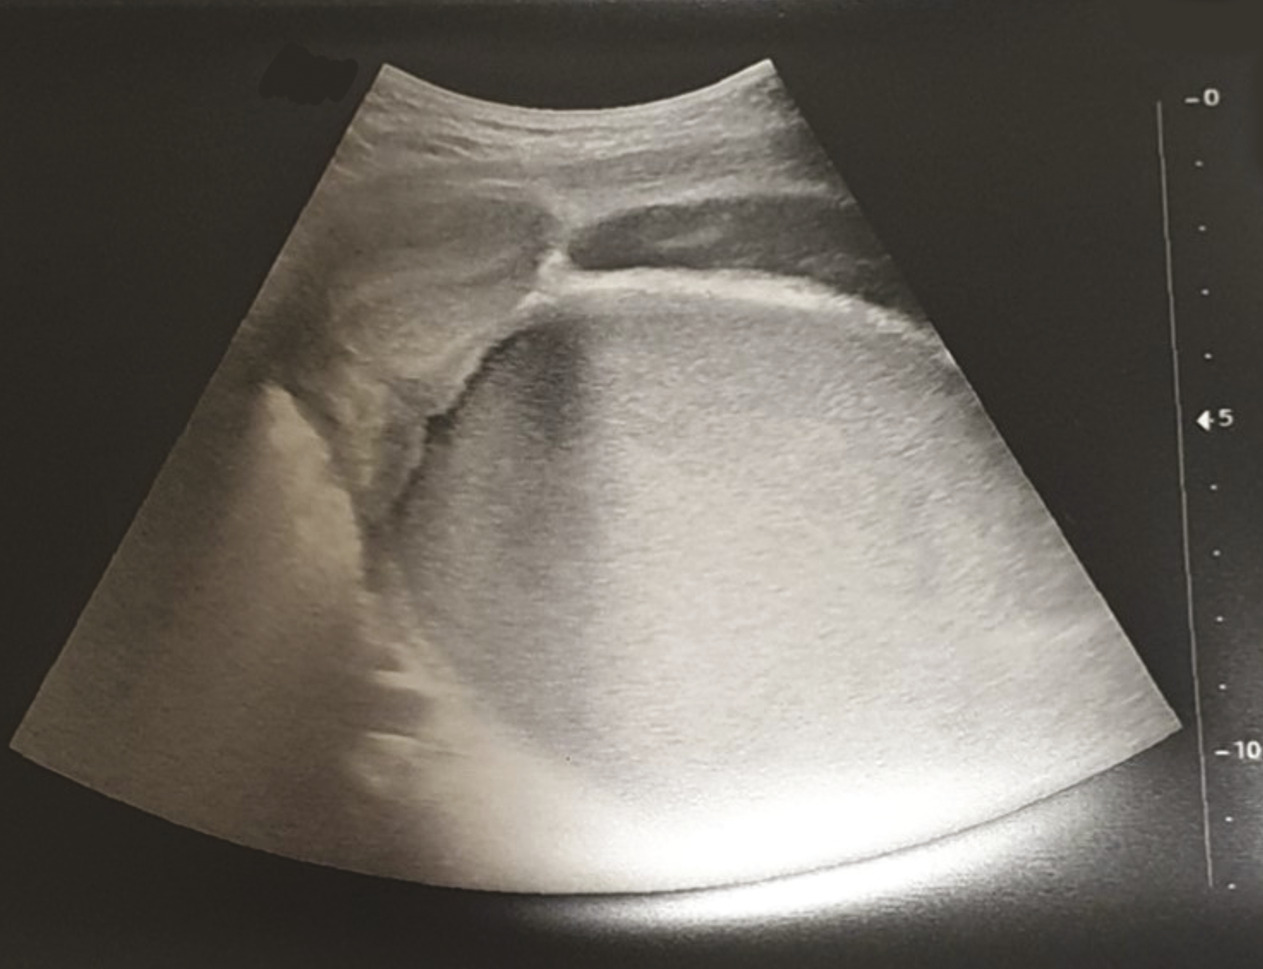

L’échographie montre une collection hématique intravaginale mesurée à 14 cm de plus grand axe correspondant à un hématocolpos secondaire à une imperforation hyménéale. Le reste de l’échographie confirme l’intégrité des organes génitaux internes et des cavités excrétrices rénales (fig. 1 ).

L’échographie montre une collection hématique intravaginale mesurée à 14 cm de plus grand axe correspondant à un hématocolpos secondaire à une imperforation hyménéale. Le reste de l’échographie confirme l’intégrité des organes génitaux internes et des cavités excrétrices rénales (